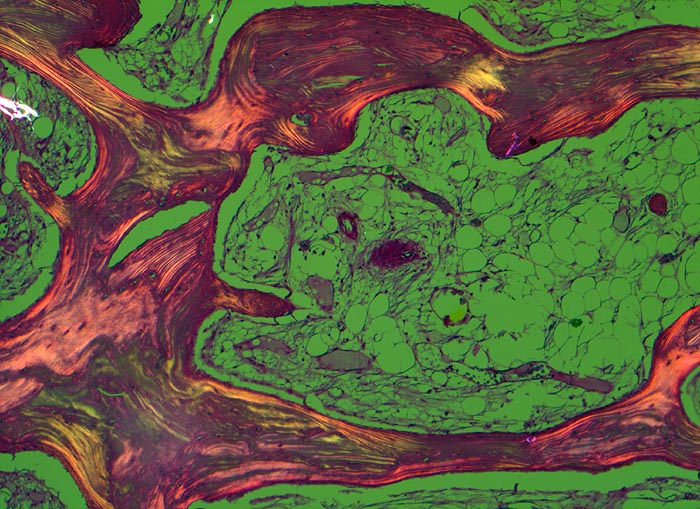

Makroskopisch ist die Nekrose im Anfangsstadium durch eine intensiv gelbe Verfärbung mit hämorrhagischem Randsaum charakterisiert. Häufig kommt es zur flächenhaften Ablösung des ansonsten intakten Gelenkknorpels (DD Arthrose!) zwischen subchondraler Knochenlamelle und angrenzender Spongiosa. In den Spätstadien sind die Nekrosezonen grau-gelb gefärbt und von körniger Konsistenz. Ein Teil der nekrotischen Spongiosabälkchen dient als Leitschiene für die Neubildung von Osteoid und mineralisierten Trabekeln, die an der Aussenseite angelagert werden. In der Nekrosezone kommt es zur Sequestrierung von Knochenbälkchen durch Frakturen. Die Markräume werden bindegewebig organisiert. In der Peripherie besteht initial ein hyperämischer Randsaum und im Verlauf kommt es zur Ausbildung einer metaplastischen Knorpel- und Knochenneubildung mit Randsklerose. Das Endstadium der Abräumreaktion untergegangener Knochenabschnitte stellt eine meist subchondral lokalisierte pseudozystische Umwandlung dar. Schliesslich kollabiert der Femurkopf und der Verlust der Gelenkkongruenz führt zu einer fortschreitenden sekundären Coxarthrose (> 3192)

• Flächenhafte Ablösung des gut erhaltenen Gelenkknorpels zwischen subchondraler Knochenlamelle und angrenzender nekrotischer Spongiosa.

• Ortsständiger Lamellenknochen wird als Leitschiene zur Fasernknochenneubildung benutzt.